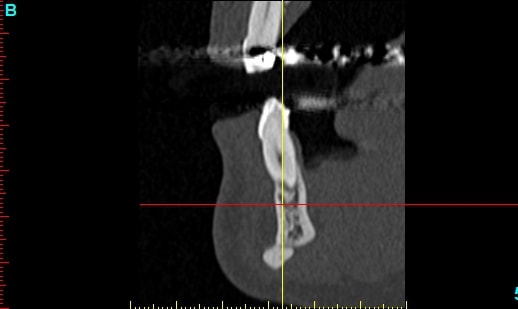

Plusieurs points: les vis de 15mm x 2mm qui transfixent c'est pas top, une seule plaque, qui plus est non réglable de chaque côté, c'est encore moins top. C'est une plaque de fracture.

En mandibulaire gauche c'est quoi ce fil d'osteosynthese? Un troisième fragment? En laissant l'apex de la 48 pile sur le trait d'osteotomie, je dis chapeau.

Pour la lésion de 42, ca peut être lié à la genio. Forage hasardeux? Mais je vote plus pour une lésion endo/paro

Celui qui a fait l'attelle, après l'ortho, lui aait dit ça permettra d'attendre après vous ferez des implants, donc je croyais que c'était une solution envisageable...avant d'avoir vu le scan.

je passerais les clichés, pour avis.

pas simple me semble t il, mais un gros avantage... la sensibilité fait partie du passé, donc je peux "planter" profond....